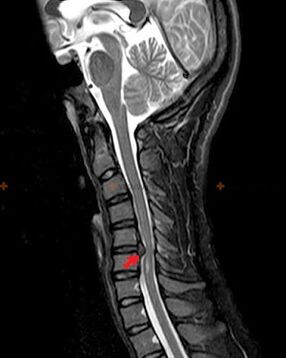

Diagnostics and X-ray signs

Osteochondrosis is an X-ray diagnosis, since a detailed clinical picture is available only at the time of exacerbation, while changes in the spine can occur with the complete subjective well-being of a person.Without an X-ray examination, we can only talk about the suspicion of osteochondrosis, because similar symptoms can be caused by other diseases (myositis, vertebral neoplasms, etc.).

The following research methods are used to diagnose osteochondrosis: radiography (preferably with functional tests), MSCT and MRI.The latter study is the most desirable due to the fact that it allows a very clear visualization of the state of the intervertebral structures.

X-ray signs of osteochondrosis include the following changes in the spine:

- Decreased height of the intervertebral discs.

- The presence of marginal bone growths.

- Injury to the position of the vertebrae in relation to each other.

- Deformations of the body and vertebral arches, etc.

The presence of the changes described above, as well as changes in the structure of the intervertebral disc, detected by MSCT and MRI, serve as reliable signs that confirm the presence of osteochondrosis.